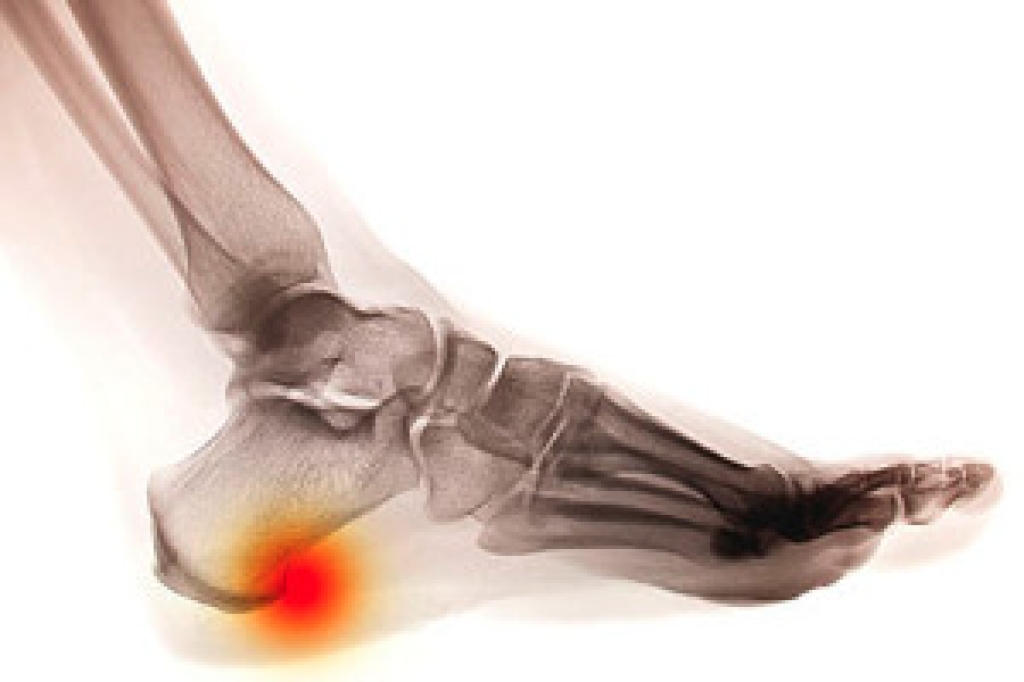

People who enjoy the sport of running and jogging are generally aware of the importance of properly stretching before starting their practice. Pointing and flexing the toes may help the feet to remain flexible, and this can be beneficial in preventing foot and ankle injuries. It is important to choose running shoes that fit properly, ensuring there is adequate room for the toes to move freely in. The muscles can become strong by incorporating strength training into your gym practice, and this can positively affect the overall health of the body. When beginning to run, it is helpful to start slowly, while gradually increasing the speed and distance. If you would like additional information about how to prevent running injuries that can affect the feet, it is suggested that you consult with a podiatrist.

There are a lot of mistakes a runner can make prior to a workout that can induce injury. A lot of athletes tend to overstretch before running, instead of saving those workouts for a post-run routine. Deep lunges and hand-to-toe hamstring pulls should be performed after a workout instead of during a warmup. Another common mistake is jumping into an intense routine before your body is physically prepared for it. You should try to ease your way into long-distance running instead of forcing yourself to rush into it.